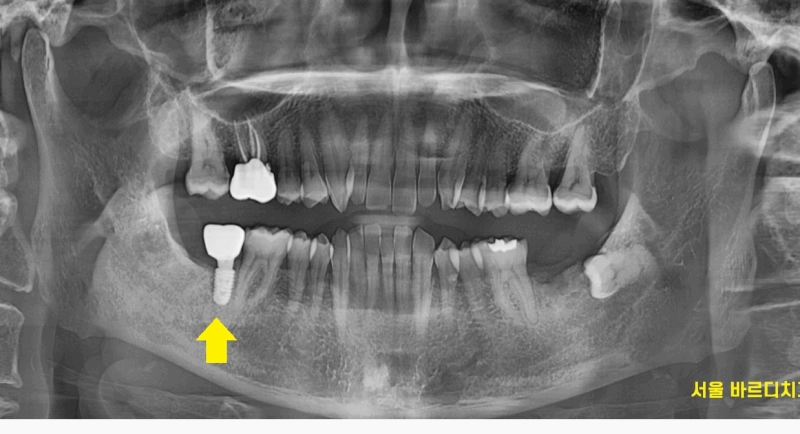

하남시청치과 처음 방문해주셨을 때

왼쪽, 오른쪽 맨 아래 끝에 어금니가 상실한 채로 오셨습니다.

ct를 분석하여

임플란트가 들어갈 각도, 사이즈 분석해줍니다!!